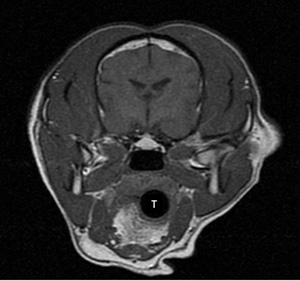

MRI: The cervical mass is located in the area of the thyroid glands, which could not be visualized. Mass is in close association with the jugular vein and internal carotid artery without evidence of invasion. The mass in the left horizontal ear canal was noted. No intracranial mass was detected.

MRI of ventral cervical mass (T = trachea):